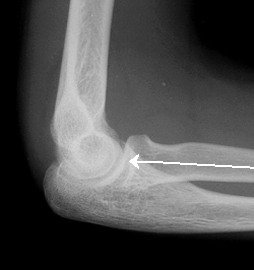

Look closely at individual parts, if dislocation look closely for tip of coronoid fragment

Look for dislocation/ subluxation of radial head

On all views (including obliques) the radial head should point to the capitellum.